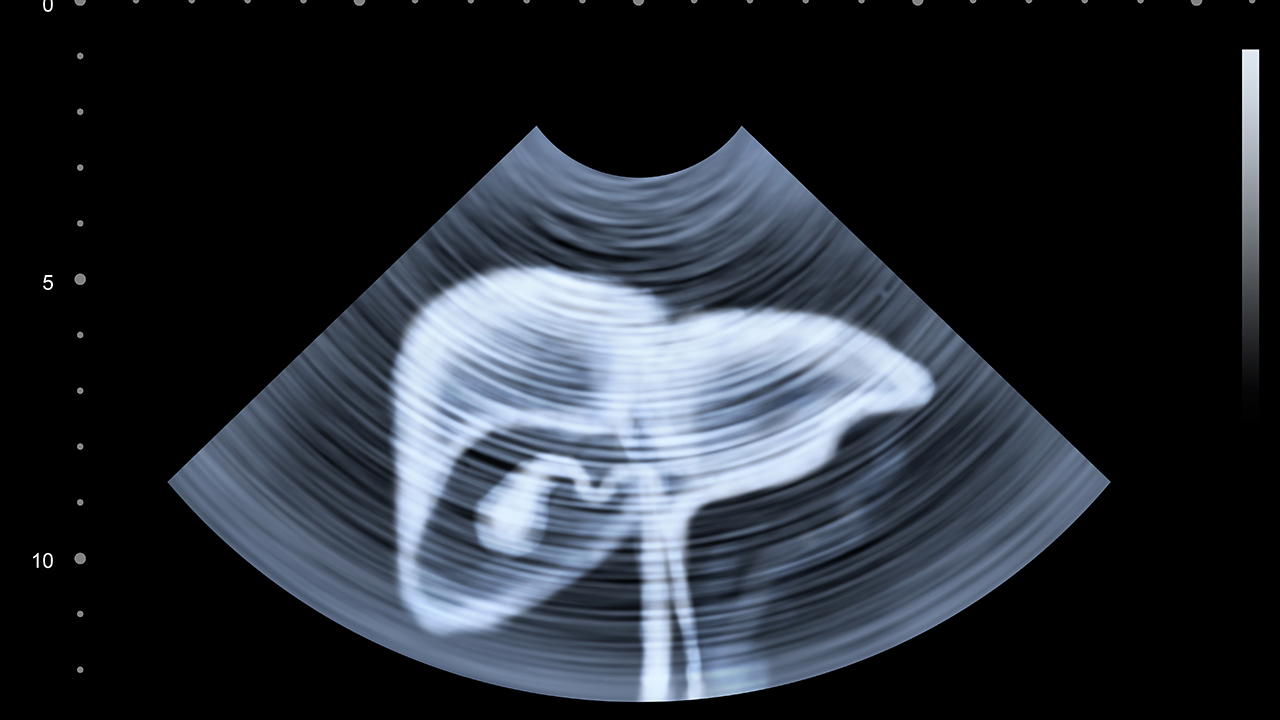

肝癌4公分,乙肝病史20年,建议及时就医,在医生的指导下进行治疗。肝癌是一种恶性程度较高的消化系统肿瘤,早期常无明显症状,多在体检时发现。随着病情进展,可出现腹痛、食欲减退、乏力、消瘦等症状。